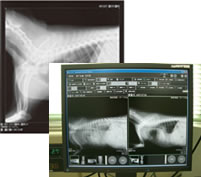

デジタルレントゲン

各種レントゲン検査

従来のレントゲンフィルムをデジタルシステムにしたもので、現像の手間がなくなり、時間の短縮ができるだけでなく、より鮮明な画像によって診断能力が向上することが期待できます。また、より少ないレントゲン線量で撮影できるため、動物の負担も少なくなります。

また、過去のレントゲン画像もコンピューターに記録しており、すぐに呼び出して比較することもできます。

この機械を、よりよい診察につなげていきたいと思います。